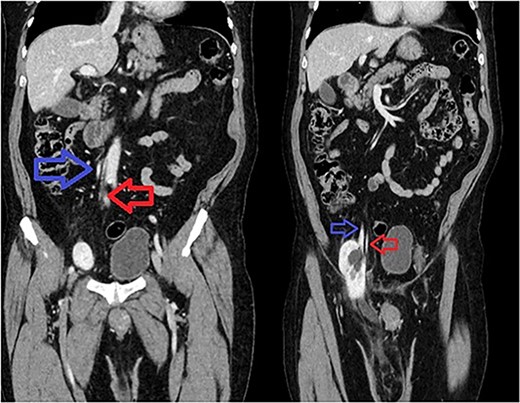

A 66-year-old Hispanic male presented to our emergency department with 1 week of right groin pain and swelling. He came to the hospital due to worsening pain. He denied any nausea, emesis or fever. He was passing gas and having bowel movements without difficulty. He denied any issues with voiding, hematuria or urinary urgency. His past medical history includes congenital deformity of his left upper extremity and past surgical history of open left inguinal hernia repair. His BMI is 32.5. His serum creatinine was 1.40 mg/dL. He had a normal white blood cell count at 9.8 × 103/UL and hemoglobin at 14.1G/DL. On examination, he had right inguinal tenderness to palpation with an obvious hernia extending to the scrotum. No skin changes were present. We were unable to reduce the hernia at bedside due to pain. A computed tomography (CT) of abdomen and pelvis with IV contrast showed herniation of the right kidney in the right inguinal hernia with the upper pole in the inguinal canal. The right renal artery and vein arose from the aorta and inferior vena cava, respectively, around the level of L1-L2 region (Fig. 1). The right ureter was incarcerated within the hernia and dilated up to 2 cm in diameter. The ureter transitions to normal caliber as it exits the hernia, concerning for obstructive uropathy (Fig. 2).

Sequential coronal CT with IV contrast. Left image showing renal artery (red) and vein (blue) arising from abdominal aorta and IVC. Right image showing descending vessels going into the incarcerated right kidney.